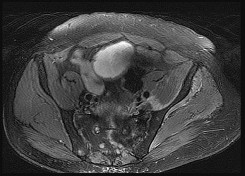

Figures 7a through 7d are the radiograph, MR images, and biopsy specimen of a 35-year-old man who has a painful, slowly enlarging knee mass. Which chromosomal translocation is characteristic of this pathology?

Synovial sarcoma is a soft-tissue sarcoma that usually occurs in young adults. Synovial sarcoma often causes pain, unlike most soft-tissue sarcomas, which generally do not cause pain. Imaging characteristics include soft-tissue calcifications on plain radiographs and a heterogeneous mass that is generally isointense to muscle on T1-weighted images and hyperintense to muscle on T2-weighted images. There are biphasic and monophasic types of synovial sarcoma. The biphasic

type, which is depicted here, has both spindle cell and epithelial components and will stain for both vimentin and cytokeratin. More than 90% of patients with synovial sarcoma have a characteristic genetic translocation of t(X;18), which results in the fusion protein SS18-SSX. This translocation can be stained for use of florescence in situ hybridization technology. t(11;12) is seen in Ewing sarcoma. T(9;22) is seen in extraskeletal myxoid chondrosarcoma. t(12;16) is seen in myxoid liposarcoma.